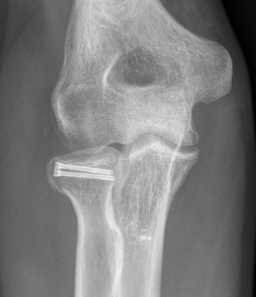

Radial Head Fixation

Indication

Significant fragment displacement

Reconstructable

Technique

Identify safe zone for implants

- posterolateral portion of cartilage / yellow and thinner, non articulating cartilage

- 90o arc between radial styloid and Lister's tubercle

- 2.5 or 3.5 headless compression screws

Complications

PIN injury

Intra-articular screws

Hardware failure

Heterotopic ossification

AVN

Non union

Radial head fragment nonunion